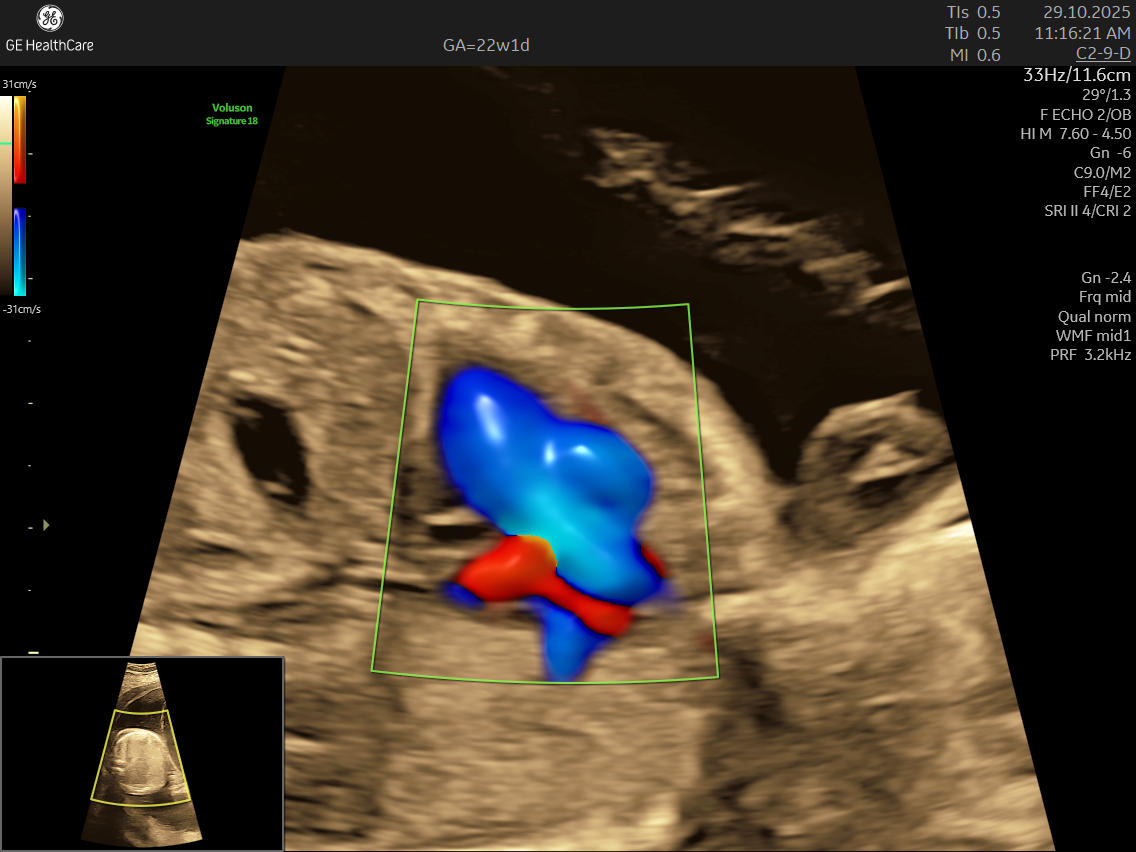

- High Detail: Utilizing advanced Doppler ultrasound technology, it tracks blood movement through the heart and valves, highlighting issues that general scans often cannot detect.

- Blood Flow Patterns: Detects arrhythmias or irregular heartbeats and checks for efficient circulation through the heart and major vessels.

- Abnormalities in blood flow patterns and valve function observed on Doppler imaging.

- Using the advanced GE Voluson S10 ultrasound machine—renowned for its superior imaging clarity, 4D real-time visualization, and automated analysis tools that significantly increase diagnostic accuracy and reduce the chances of missing subtle heart defects.

- Its a specialized ultrasound done between 18–24 weeks of Gestational Age that evaluates the structure, function, and rhythm of a baby’s heart while still in the womb. This scan uses high-frequency sound waves to create detailed images of the fetal heart, aiding in the detection of congenital heart defects (CHDs) and other abnormalities.